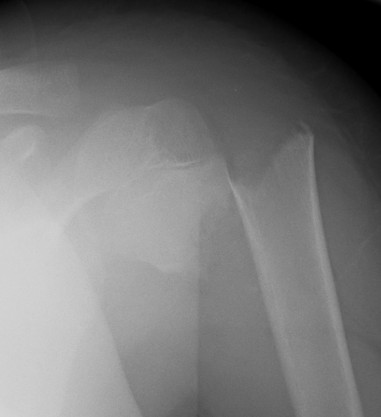

Case: 18 year old boy

Initial xray 18 month xray